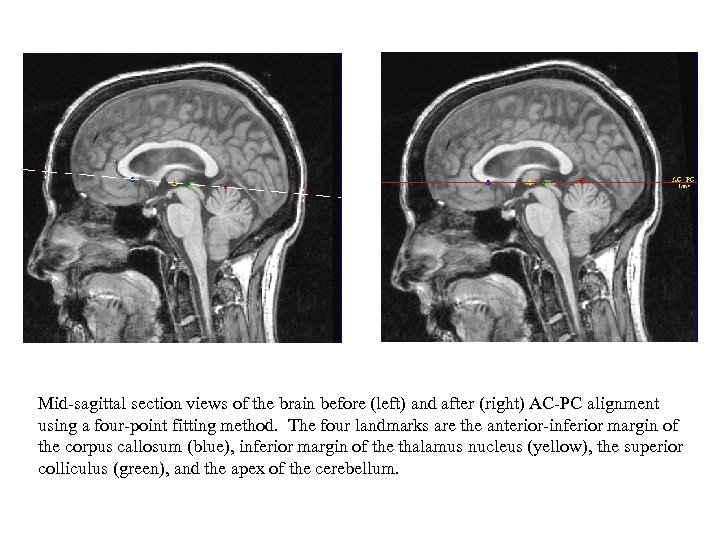

Mid-sagittal section views of the brain before (left) and after (right) AC-PC alignment using a four-point fitting method. The four landmarks are the anterior-inferior margin of the corpus callosum (blue), inferior margin of the thalamus nucleus (yellow), the superior colliculus (green), and the apex of the cerebellum.